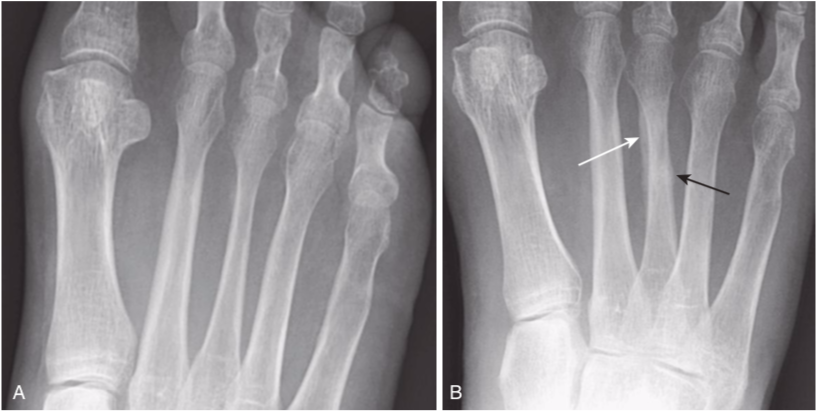

Stress fracture, two frontal views taken 5 weeks apart.

A,Although conventional radiographs are the study of first choice, they may initially appear normal in as many as 85% of cases of stress fractures, so it is common for a patient to complain of pain yet have a normal-appearing radiograph, as seen here one day after pain began. B,The fracture may not be diagnosable until after periosteal new bone formation forms (white arrow)or, in the case of a healing stress fracture of cancellous bone, the appearance of a thin, dense zone of sclerosis across the medullary cavity (black arrow). This radiograph was taken 5 weeks after the first.